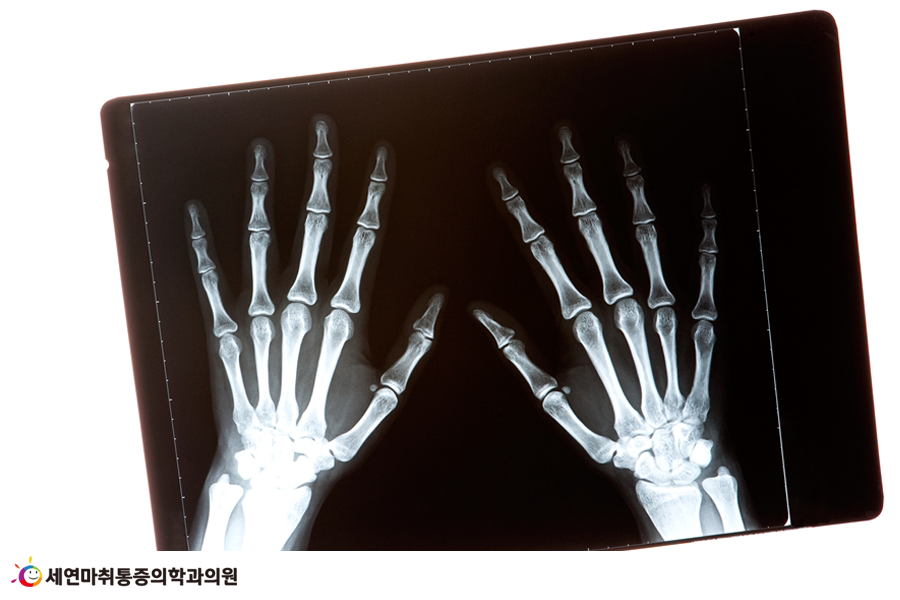

수근관이란 손목 앞쪽 피부조직 밑에 뼈와 인대가 있는 작은 통로로 ‘손목터널’이라고도 부릅니다. 그래서 수근관증후군을 흔히 손목터널증후군이라고 부르는 것이지요.

수근관에는 9개의 힘줄과 하나의 신경이 손가락 쪽으로 뻗어 있는데, 이곳에는 ‘정중신경(median nerve)’이 지나갑니다.

수군관증후군이란 여러 가지 원인으로 인해 손목의 인대가 두꺼워지면서 인대 사이를 지나가는 정중신경이 눌려 통증을 유발합니다. 손목 안쪽의 피부 아래 뼈와 인대 사이 통로가 좁아져서 발생하는 질환입니다.

수근관을 지나가는 정중신경은 엄지손가락과 둘째, 셋째, 넷째 손가락과 이어져, 엄지손가락의 감각에 영향을 주는 신경입니다.